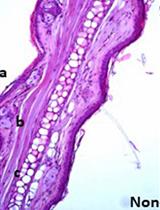

The intratracheal instillation technique is used to deliver a variety of agents to the lungs ranging from pathogens (bacteria, viruses), toxins, to therapeutic agents. To model lung inflammation and injury, LPS can be administrated via intranasal, intratracheal, or aerosol approaches. Each technique has its limitations. The intratracheal technique can involve the non-invasive instillation method (via the oro-tracheal route) or a direct injection into the trachea. Here, we describe an optimized method for direct visual instillation of LPS via the non-invasive oro-tracheal route.

This protocol describes the procedure for the direct visual instillation method for intratracheal (i.t.) instillation (Su et al., 2004) of LPS.